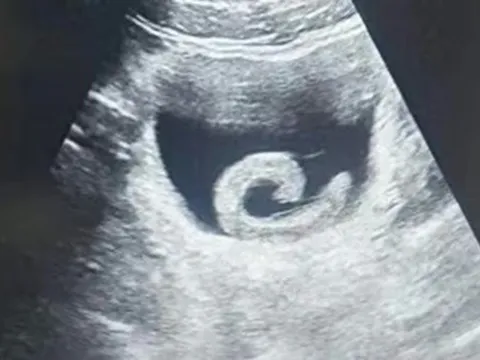

Qua thăm khám, các bác sĩ ghi nhận tử cung to ngang rốn, tương đương thai khoảng 20 tuần, kết quả siêu âm cho thấy nhân xơ tử cung kích thước lớn, khoảng 147 x 135 x 134 mm. Bệnh nhân được chẩn đoán nhân xơ tử cung to và được chỉ định phẫu thuật bóc nhân xơ tử cung.